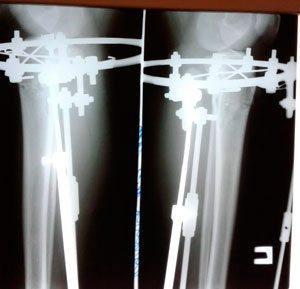

Дата операции - 15.07.2019г.

Дата снятия аппаратов - 15.10.2019г.

Срок сращения 90 дней.